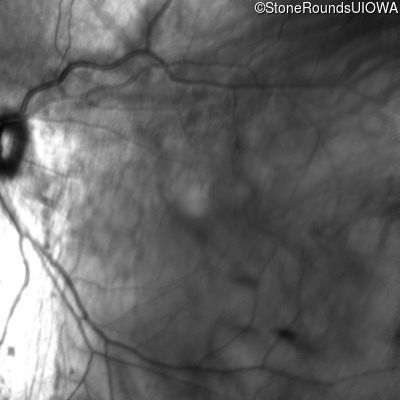

Age at visit: 41 years (Visit 2)

This 41 year old woman was highly myopic as a child and experienced a rhegmatogenous retinal detachment OS at age 20.

The clinical features favoring the diagnosis of Sticker syndrome in this patient include extensive radial lattice degeneration, a personal and family history of rhegmatogenous retinal detachment, a history of cataract surgery before age 30 (and very high myopia before that), arthritis in her knees and hips and a slightly flattened mid-face.